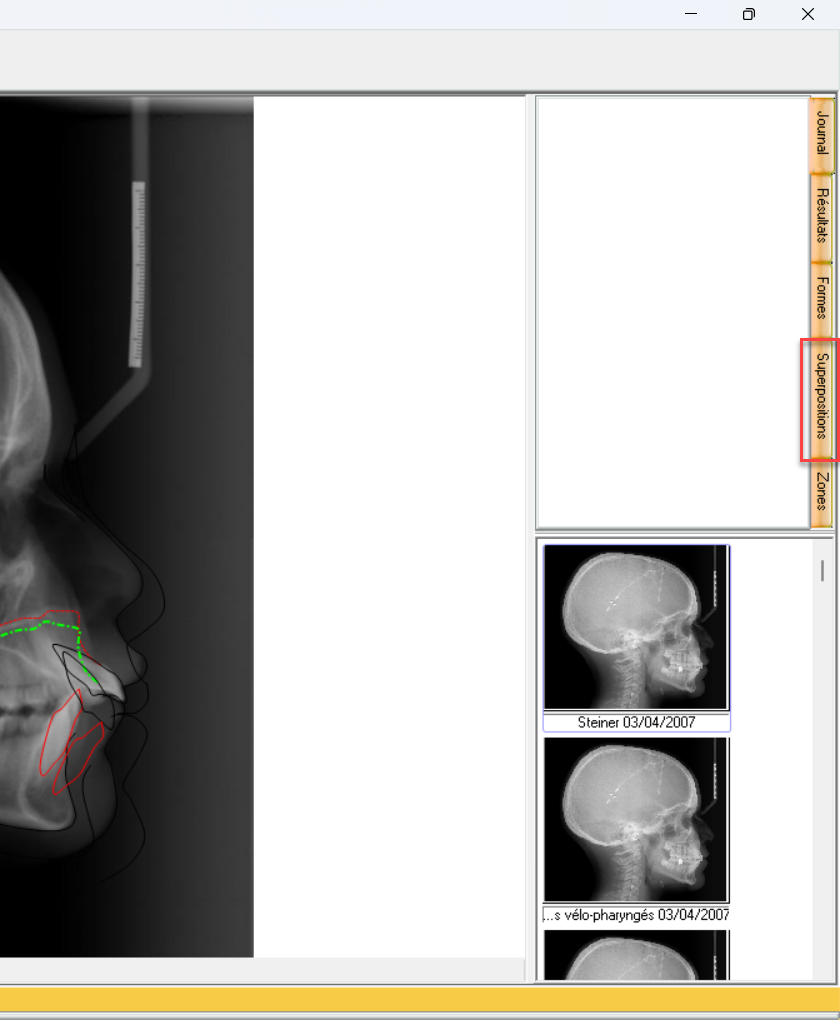

Pour choisir une superposition avec un plan (donc points) différent, allez sur onglet Superposition a droite de la fenêtre générale.

De cet onglet vous aurez accès à la liste des plans de superposition.

Sur cet exemple, nous choisissons Sur Na.A en A.